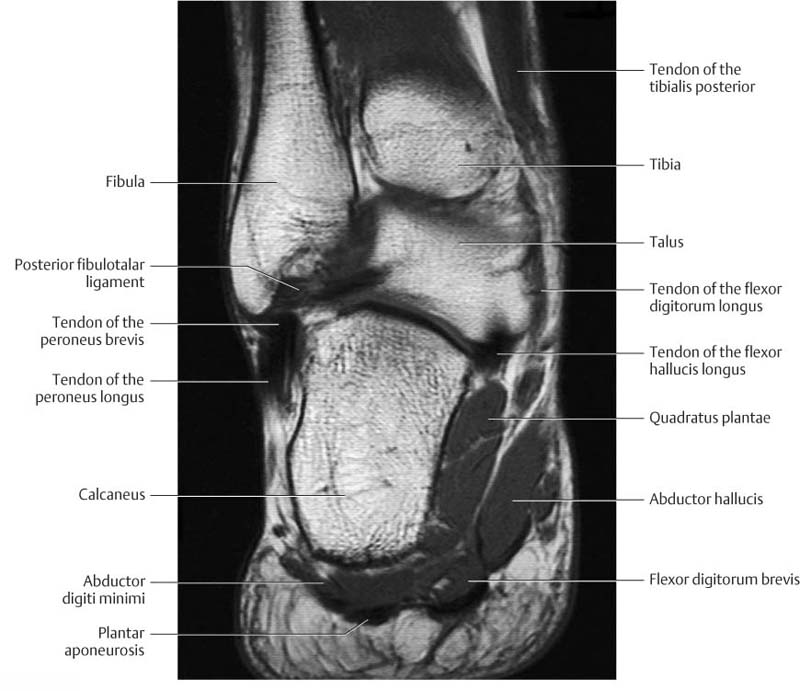

Normal Magnetic Resonance Imaging Anatomy Of The Ankle & Foot

www.mri.theclinics.com

www.mri.theclinics.com

ankle anatomy foot mri normal coronal resonance imaging t1 magnetic fig

Normal Magnetic Resonance Imaging Anatomy Of The Ankle & Foot

www.mri.theclinics.com

www.mri.theclinics.com

mri anatomy foot ankle normal plantar muscle tissue resonance magnetic imaging res hi soft gr10

Normal Magnetic Resonance Imaging Anatomy Of The Ankle & Foot

www.mri.theclinics.com

www.mri.theclinics.com

mri foot ankle anatomy cuboid normal ligament lateral calcaneocuboid calcaneal joint magnetic resonance imaging figure tuberosity large